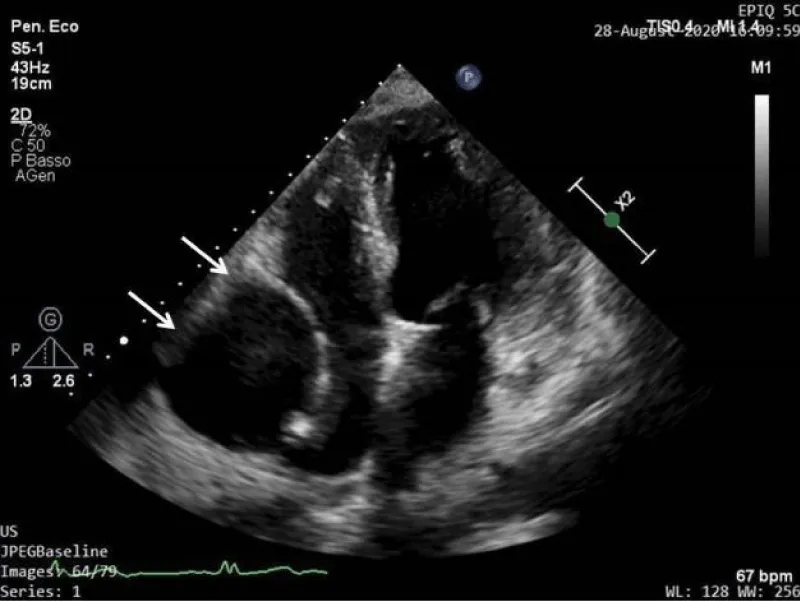

We performed echocardiography that showed normal size and function of the left ventricle and confirmed the presence of a giant round cystic-appearance lesion at the level of the right atrioventricular groove with mild compressive effect on the right chambers. The lesion was characterized by the presence of an anechoic space with an internal echogenic swirling flow pattern (Figure 2). The color Doppler mode showed a faint signal, without clear evidence of flow origin and it was not possible to sample any conclusive PW-Doppler signal.

Figure 2: 2D echocardiography (4 chamber view) shows the presence of a giant round cystic-appearance lesion characterized by the presence of an anechoic space with an internal echogenic swirling flow pattern.

We also performed a bubble test with agitated saline contrast medium injected through the right and left antecubital vein, without evidence of any contrast uptake by the mass.

We firstly excluded a pericardial cyst because of the echo appearance of the lesion with anechoic space and internal echogenic swirling flow pattern, highly suspicious for blood flow. To better characterize the flow, color-Doppler and PW-Doppler were performed with inconclusive results. The bubble test also excluded communication between the lesion and right cardiac chambers or systemic veins.